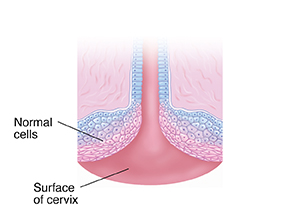

Normal cells in the cervix flatten as they grow. They form a protective layer as they move toward the surface of the cervix.